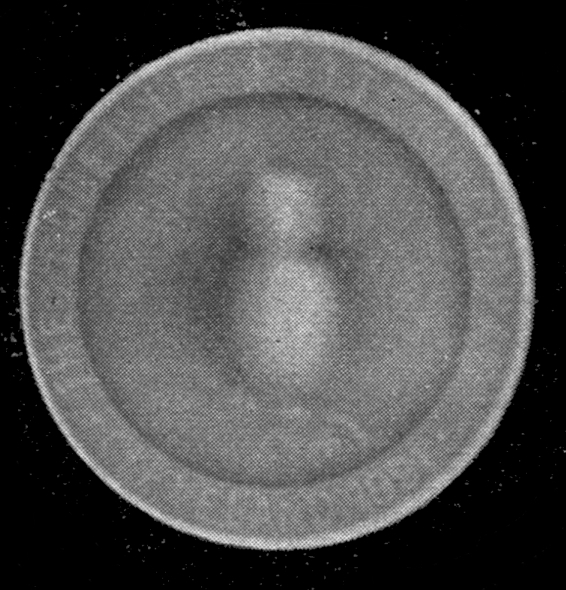

Fig. 1.—Head.

Fig. 2.—Broken Arm, Overlapping.

(Due to defective setting.)

Fig. 3.—Ribs.

Fig. 4.—Knee, Knickerbocker Buttons, Bullet in Femur.

FROM SCIAGRAPHS BY PROF. DAYTON C. MILLER. § 204.